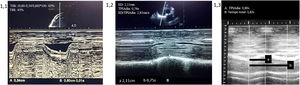

Las mediciones diafragmáticas fueron realizadas por médicos intensivistas con entrenamiento en ultrasonografía crítica utilizando un ecógrafo Sonocare (modelo Sonosite EDGE 03VRYF). Se utilizó un transductor de 1-5MHz para la evaluación en modo-M de la excursión diafragmática (ED, cm), el tiempo de inspiración (TPIAdia, s), la velocidad de contracción del diafragma (ED/TPIAdia, cm/s), y el tiempo total (Ttot, s); la fracción de engrosamiento (TFdi, %) se evaluó con transductor de 6-13MHz en modo-M (fig. 1 y tabla 2). Se definió disfunción diafragmática como ED<1cm o movimiento paradójico18.

Medidas ecográficas utilizadas para evaluar el éxito en la retirada de la ventilación. Medias en modo M. 1,1: Fracción de engrosamiento (TFdi, %), grosor espiratorio (A), grosor inspiratorio (B). 1,2: Medición de la excursión diafragmática (a) (ED, cm), tiempo de inspiración (b) (TPIAdia, seg), velocidad de contracción diafragmática (ED/TPIAdia [cm/seg]). 1,3: Tiempo de inspiración (a) (TPIAdia, seg), tiempo total (b) (seg).